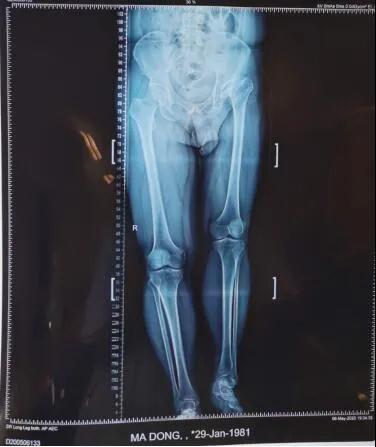

19日,beat365在线唯一官网第六附属医院骨病矫形外科主任李璐兵向记者透露:预计3个月后,有望像正常人一样自如行走。当日,记者在病房走廊看到,马先生手扶助行器,正在练习行走。“17日手术的,今儿就可以下地了。”马先生说。39岁的马先生,年幼时就患有左髋化脓性关节炎,因当时治疗条件有限,造成后期左髋关节骨质破坏严重,左下肢比右下肢短缩了6厘米,走路时跛行很明显,加上左髋关节因为骨质破坏严重导致活动范围受限,就连穿袜子都需要别人帮助。

同时,患者左侧肢体长时间处于短缩状态,髋关节活动受限,周围的肌肉、软组织弹性差,需要进行大范围的组织松解后才有可能将置换后的髋关节准确复位,而松解的过程中最大的风险在于损伤周围的重要血管神经导致大出血。

整个手术进行了两个小时,将置换后的髋关节假体准确复位,为患者重建了髋关节并且矫正两条腿基本恢复等长。